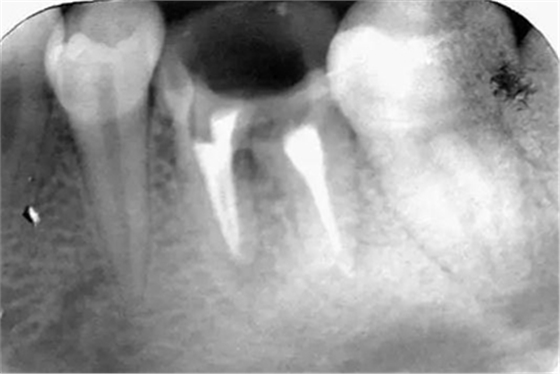

主尖銼X光片:

G鉆預(yù)備:

預(yù)備后:

根充后: